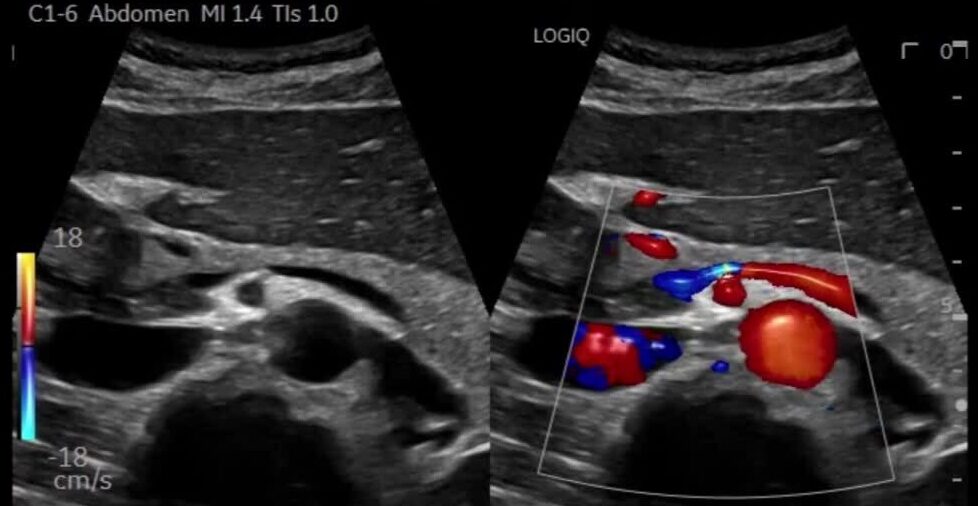

Ultrasound imaging, also called ultrasound scanning or sonography, uses a small transducer (probe) and ultrasound gel placed directly on the skin. High-frequency sound waves are transmitted from the probe through the gel into the body. The transducer collects the sounds that bounce back, and a computer then uses those sound waves to create an image.

High-frequency sound waves are transmitted from the probe through the gel and into the body. The transducer collects the sounds that bounce back, and a computer then uses those sound waves to create an image.